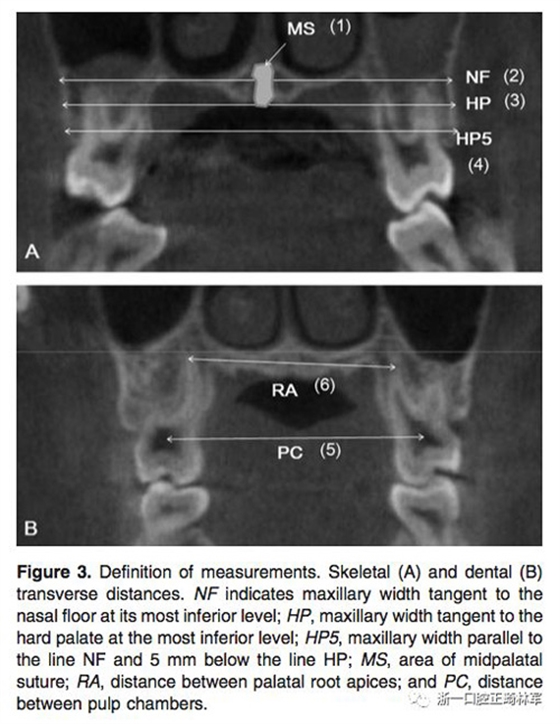

在治療前(T1)和擴弓后3個月(T2)拍攝CBCT,獲得的數據由In Vivo Dental(Anatomage,San Jose,Calif)分析。為了在T1和T2階段設置相同的參考平面,CBCT圖像沿著腭中縫(x平面)定向,平行于腭平面(y平面)并且與鼻底(z平面)相切(Figure 2)。在腭中縫處評估橫向骨骼擴張,并在三個不同的平面進行線性測量:鼻底,硬腭和硬腭以下5mm。在根尖和牙冠水平測量橫向牙齒擴張(Figure 3)。評估兩側的牙槽傾斜度,牙長軸,牙齒垂直高度和骨開裂等情況(Figure 4,5)。所有測量均在每個上頜前磨牙和磨牙區(qū)域進行。